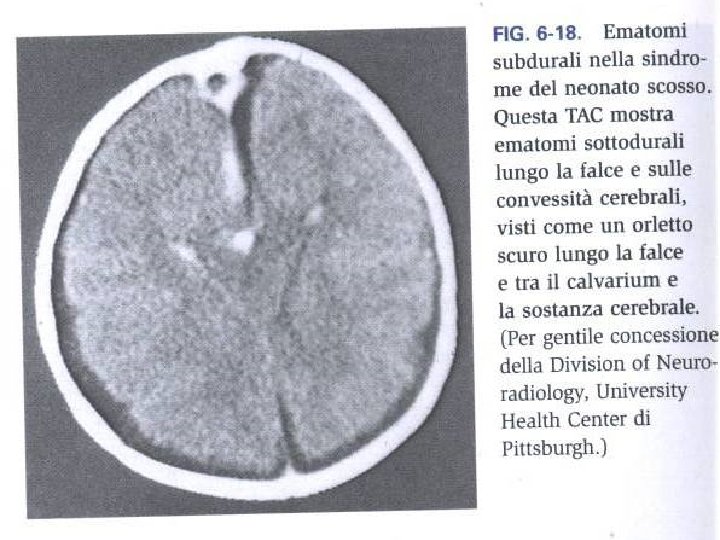

Il bambino vittima di abuso Abuso o maltrattamento fisico: aggressione fisica volontaria che produce lesioni fisiche o mentali. Localizzazioni anomale per incidenti accidentali: centrali sul corpo o sul collo e riguardanti bambini non deambulabili. Ustioni: da contatto o da immersione. Sono particolarmente sospette quelle da sigaretta Fratture sospette: sotto l’anno d’età, bilaterali, risalenti ad epoche diverse, multiple, a carico delle coste Traumi del SNC: ematomi, fratture, emorragie intracraniche. Il trauma da scuotimento “shaken baby sindrome” è tipico delle violenze ed è caratterizzato da: emorragie retiniche, subdurali, edema cerebrale, fratture costali e metafisarie